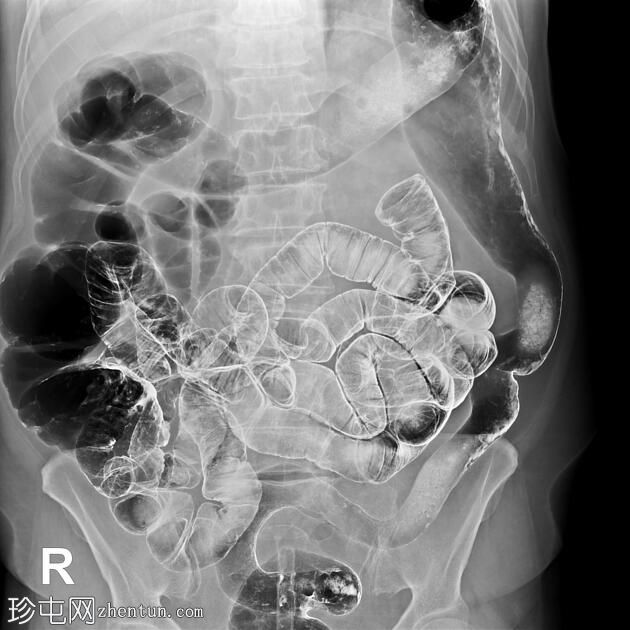

结肠异常表现包括结肠袋皱襞消失,使其外观模糊,呈铅管样改变。

其他异常表现包括降结肠和乙状结肠肠袢狭窄,以及横结肠和降结肠多处黏膜糜烂(双对比增强图像可见)。

未见肿块或瘘管形成。

升结肠外观正常,结肠袋皱襞完整。

结肠镜检查和活检结果显示为溃疡性结肠炎,属于炎症性肠病。

结肠呈铅管状外观是慢性炎症性肠病(溃疡性结肠炎)的典型放射学表现。